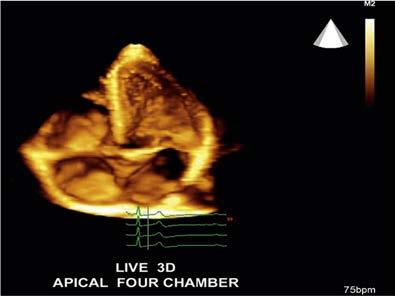

while still being used extensively, has been extended to 3D scanning and imaging, also called volume imaging. This method requires scanning the ultrasound through many adjacent 2D tissue cross-sections to compose a 3D volume of echo information similar to a loaf of sliced bread (Figure 1-11). This 3D volume of echoes can then be processed and accessed to present 2D or 3D images of the anatomy.

FIGURE 1-11 Three-dimensional (volume) sonographic images. A, Three-dimensional echo data acquired by obtaining many two-dimensional sections of echo information (colored slices) from the imaged anatomy, forms a three-dimensional volume of stored echo information (blue box). B, Cardiac four-chamber view. C, Fetal head.